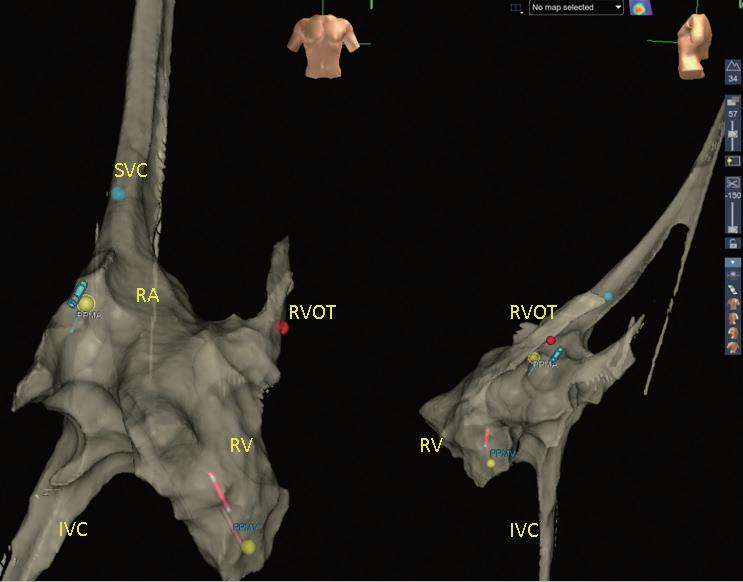

術製造皮下口袋(subcutaneous pocket)後,再以導線 經 Seldinger technique 建立靜脈的通道。接著,藉由 EnSite Precision 心臟定位系統,使用可控式 10 極導管 ( InquiryTM, steerable diagnostic catheter, SJM ), 自左鎖骨下靜脈、頭肱靜脈 , 上、下腔靜脈、右心房 以及右心室等立體結構,進行心血管系統之 3D 繪製 (圖二)。繪製時,會特別著重右心耳、右心尖與右 心室出口的結構與位置,以利後續置放進行。接著, 將心臟植入性電子儀器的導線連結於 EnSite 系統並成 像,在 3D 定位系統導引下,由先前繪製的構造中, 將導線尖端置於目標處(圖三),並進行相關參數測 試。選定適當位置進行導線固定時,由於目前系統無 法將主動固定的螺旋( screw)成像,因此無法確認螺 旋是否確實伸展。我們團隊於此步驟會藉由螢光檢查 檢視螺旋伸展的狀況、評估放置位置是否與預期相符 以及導線鬆弛程度( lead slack)是否適當。調整後, 完成心臟植入性電子儀器放置時,亦會再藉由螢光檢 查確認位置(圖四)。目前臺大單一中心經驗,藉由 3D 定位系統於 13 個病人中放置過 14 個儀器(3 個單 腔節律器、6 個雙腔節律器、4 個植入式心內去顫器及 1 例心臟再同步治療裝置),平均輻射暴露時間約為 0.6 分鐘,相較於傳統方式(平均輻射暴露時間為 10.3 分 鐘)明顯少許多。目前無觀察到相關術後併發症,且 各儀器的追蹤參數與傳統置入的儀器無差別。 相較於置放節律器與植入式心內去顫器,心臟再 同步治療裝置的更為複雜,因為需將導線置於冠狀 靜脈竇(coronary sinus, CS),可能需要藉由顯影劑 讓 CS 顯像,且所需的輻射暴露時間常為前兩者的數 倍 (14),病人與執行醫師的輻射暴露也最強,過去甚至 有研究建議一位醫師單月放置心臟再同步治療裝置數 目勿超過四個,以控制在較安全的輻射曝露量 (15)。

中華民國心律醫學會‧ Taiwan Heart Rhythm Soclety ‧中華民國 111 年 9 月出刊 ( 圖三 ) ( 圖ㄧ ) ( 圖二 ) ( 圖四 ) vs 101.4 秒 , p<0.001),16 位無輻射導引組執行過 程 的輻射暴露時間 < 1 秒,使用於螺旋旋入後之確認影 像,兩組病人於手術當下、一週與 4 到 6 週的追蹤皆 無併發症,並且於追蹤導線電阻(impedance)、相關 閾值(包括 capture voltage, capture time)等皆無差別, 可謂兩組放置成效相仿 (16)。對於使用無輻射導引置放 CIED 的過程,何時要使用螢光檢查確認,依不同醫學 中心的習慣而異。有個案報告於懷孕婦女中,在術中 以心臟內超音波評估導線鬆弛程度(lead slack);或 以更換不同曲度的探針( stylet)而導線尖端位置維持 不變,做為螺旋順利旋入的間接證據,來達成完全零 輻射暴露的 CIED 置放。然而大部分的中心,仍常規 於螺旋固定後,以螢光檢查影像進行相關確認 (10,11,16)。 當面臨血管解剖構造有變異、導管產生糾結或是冠狀 靜脈竇無法完整繪製的狀況,螢光檢查仍佔重要的輔 助角色 (11)。 3D 定位系統於介入性心臟電生理學的領域,未來將 佔據更重要的角色,對於構造複雜的先天性心臟病患者, 因其血管走向常不典型,過往治療可能造成多處心肌纖 維化或高度累積輻射暴露,以無輻射導引方式進行介入 性心臟電生理治療與儀器置放,有其優勢與必要性 (17)。 現階段因為各國技術上仍未標準化,此技術尚未普及, 也缺乏大型研究分析其成效與安全性,針對長期預後以 及是否符合成本效益,還有賴未來研究證實。不過在執 行數量增加後,執行時間預期可以降低且可大幅度降低 輻射暴露,相信在不久的未來,能為病患與醫療團隊, 建構更安全、有效率的醫療環境。